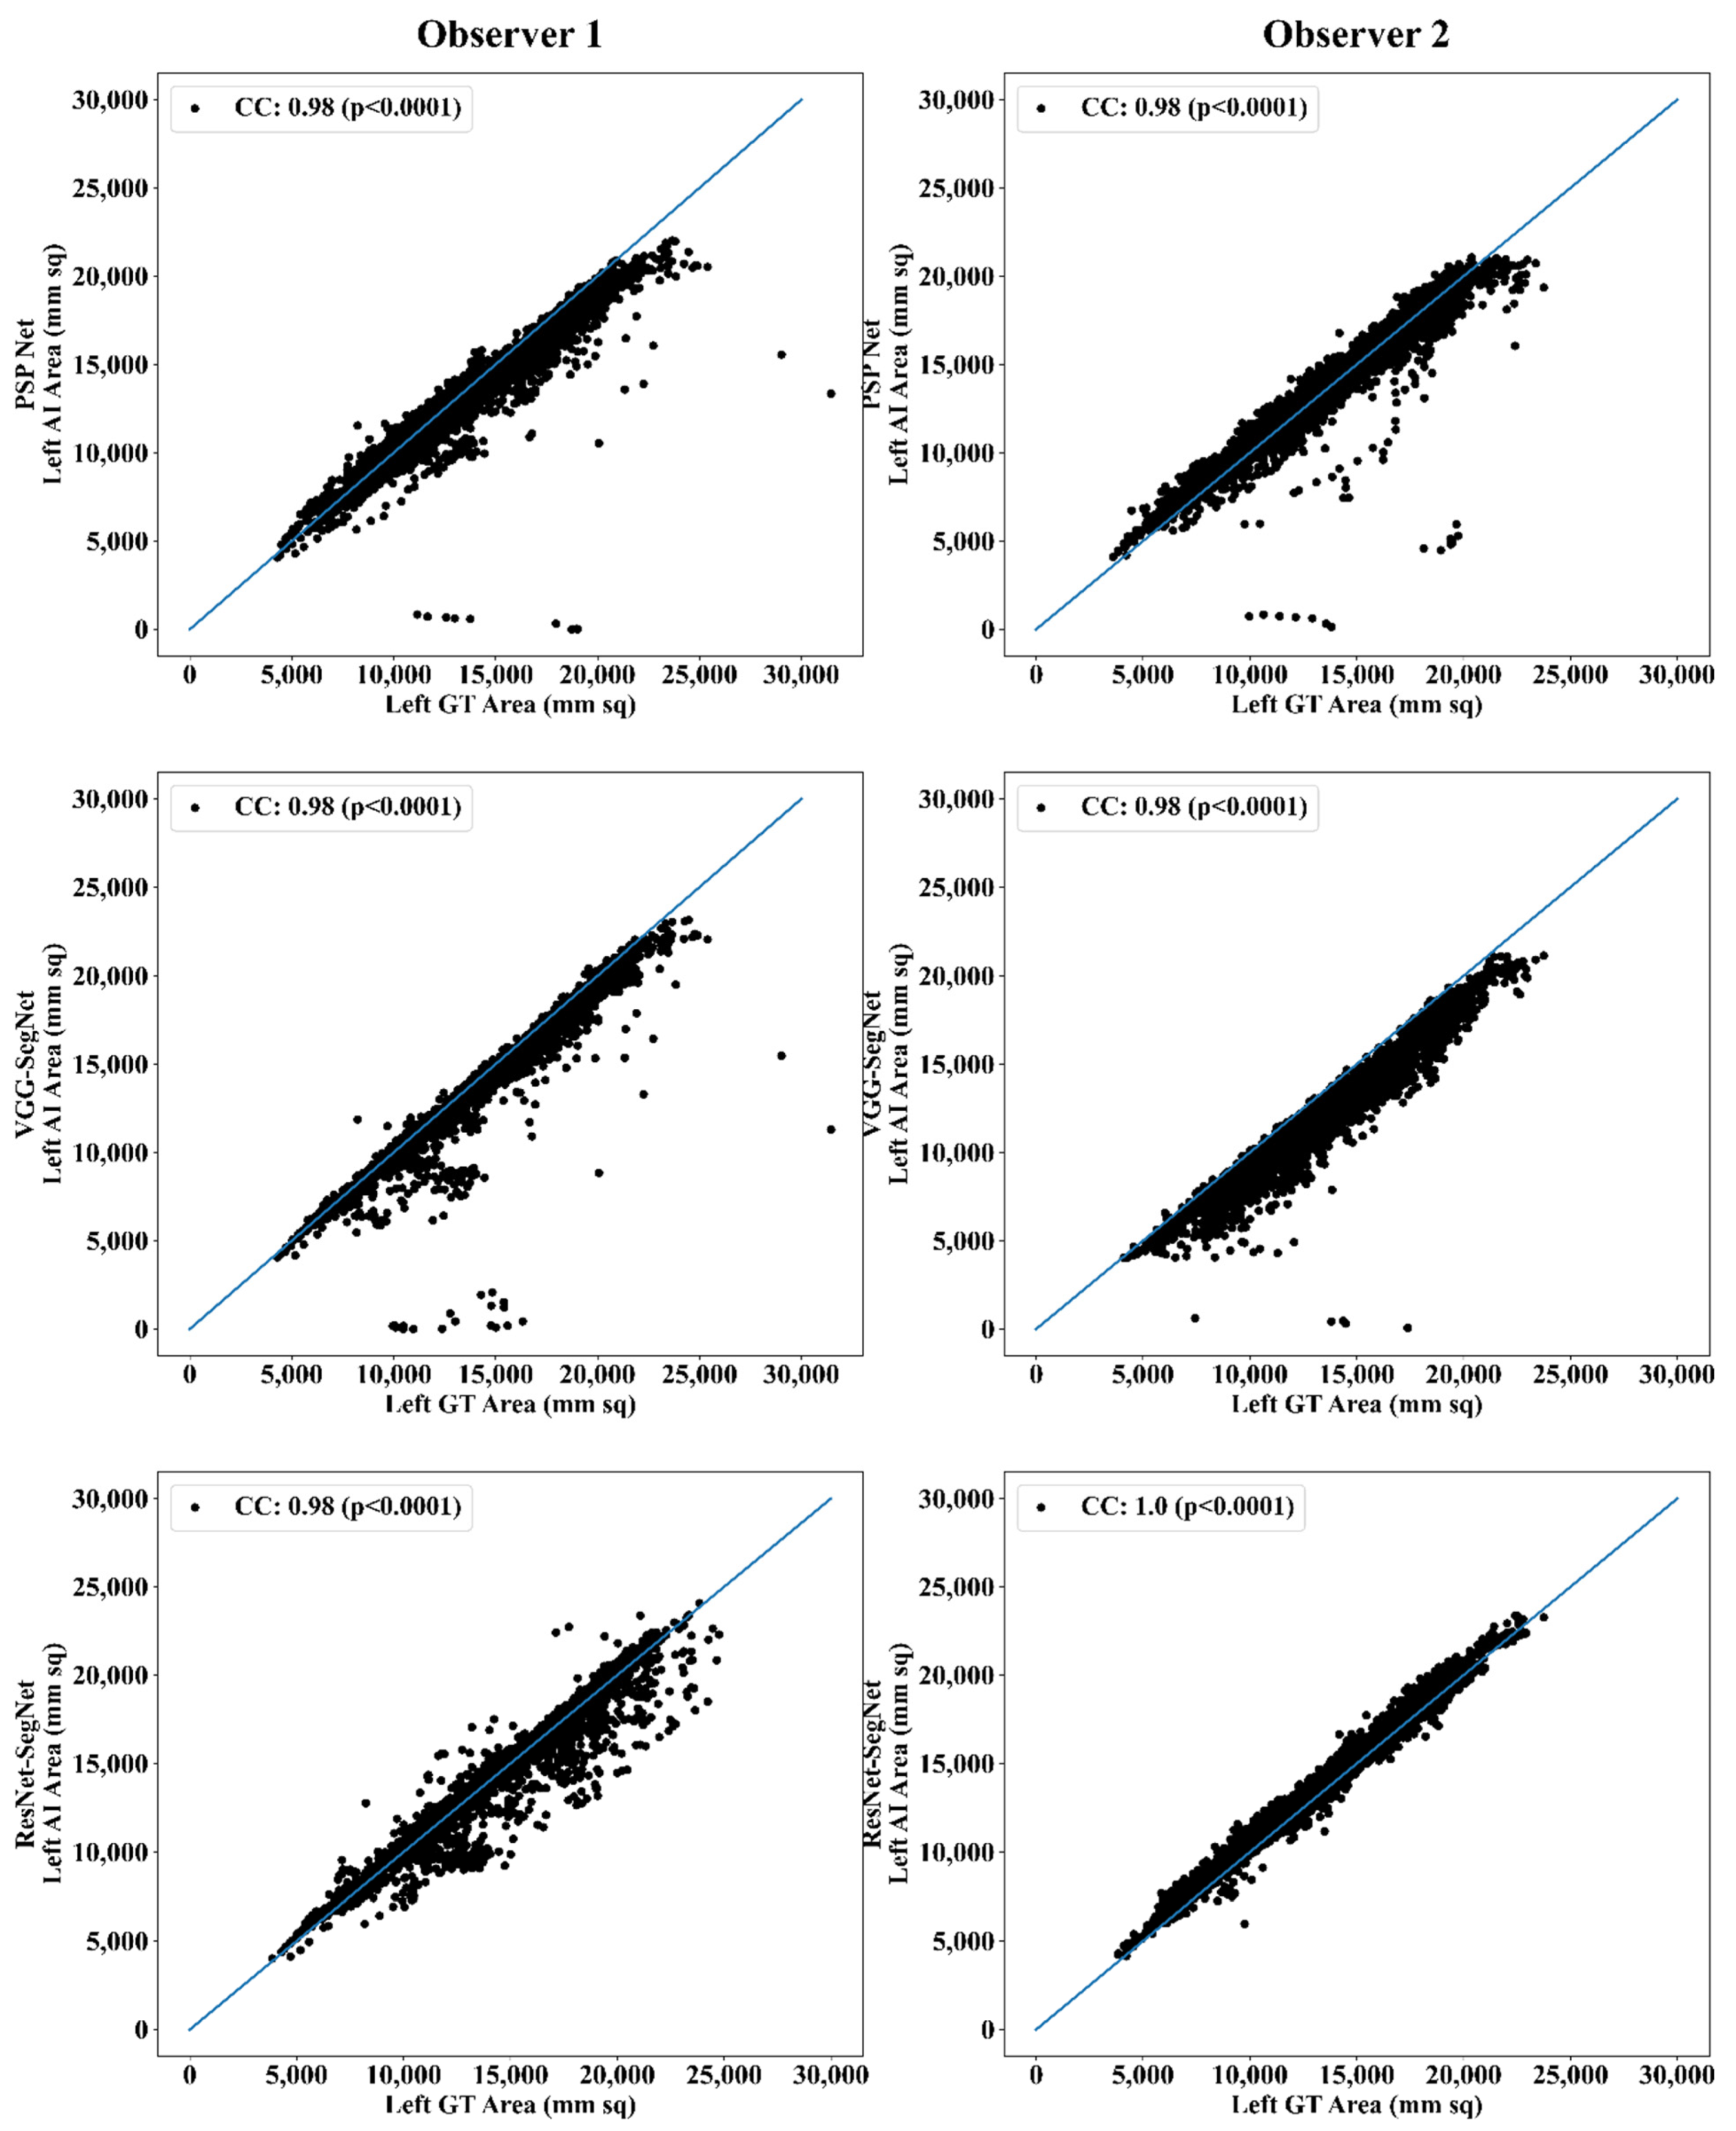

Correlation Plot for Lung Area Error